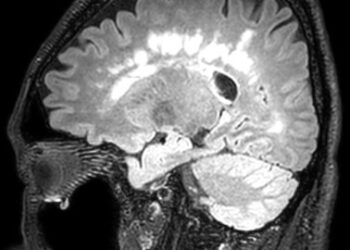

ЧИТАТЬ ВСЕЦеребральная аутосомно-доминантная артериопатия с подкорковыми инфарктами и лейкоэнцефалопатией (CADASIL) является наследственным заболеванием мелких сосудов, проявляющимся в виде повторяющихся ишемических событий,...

ЧИТАТЬ ВСЕНедавно завершенное многоцентровое клиническое исследование фазы 3 показало, что иммуномодулирующий препарат может подавлять активность воспалительного заболевания у подавляющего большинства пациентов...

ЧИТАТЬ ВСЕОфатумумаб, который в настоящее время находится на стадии 3 испытаний, показывает многообещающие результаты в значительном уменьшении симптомов рассеянного склероза. Крупное...